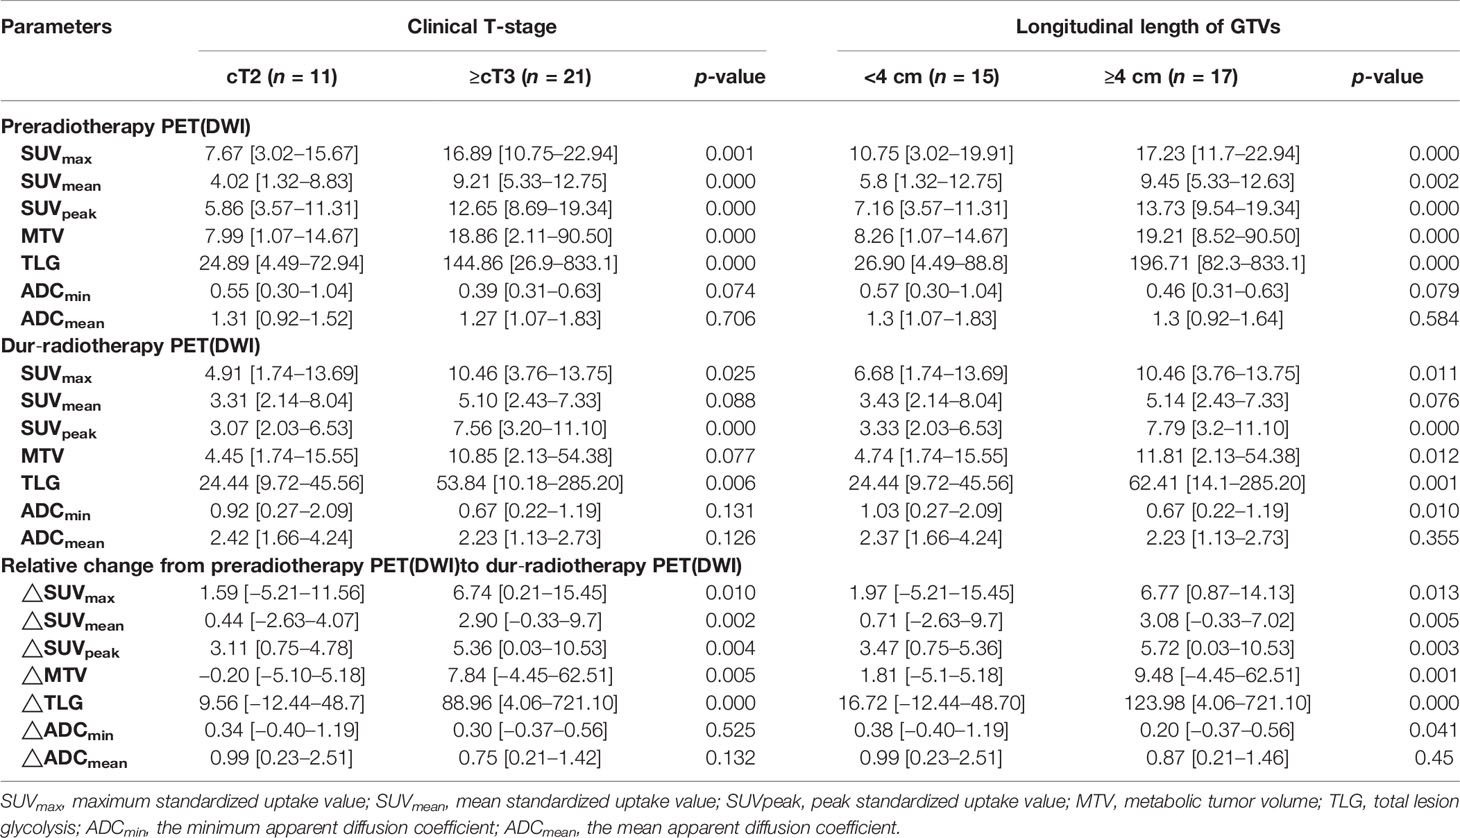

Associations of SUVs and ADCs With Clinical Prognostic Factors

Table 4 shows associations of SUVs and ADCs with clinical T-stage and longitudinal length of GTVs. The SUVs (SUVmax, SUVmean, and SUVpeak), MTV, and TLG pre-RT and its relative changes between pre-RT and after 15 fractions of RT were significantly higher in stages T3–4 than in stage T2 and in the group with a longitudinal length of GTVs ≥4 cm than <4 cm (p = 0.000−0.041). The ADCmin dur-RT and its relative changes between pre-RT and after 15 fractions of RT were significantly lower in the group with a longitudinal length of GTVs ≥4 cm than <4 cm, but these were not significantly associated with clinical T-stage (Table 4).